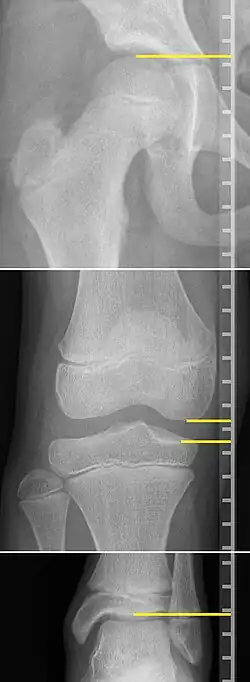

On X-rays, there is generally measurement of both the femur and the tibia, as well as both combined.[4] Various measuring points for these have been suggested, but a functional method is to measure the distances between joint surfaces:[4]

- Femur length: The superior aspect of the femoral head and the distal portion of the medial femoral condyle.

- Tibial length: The medial tibial plateau and the tibial plafond

Clinical measurement of leg length conventionally uses the distance from the anterior superior iliac spine to the medial malleolus.[11] Projectional radiographic measurements of leg length have two main variants:[12]

- Orthoroentgenogram, which takes separate images of the hip, knee and ankle.

On X-rays, the length of the lower limb can be measured from the proximal end of femoral head to the center of the plafond of the distal tibia.[13]